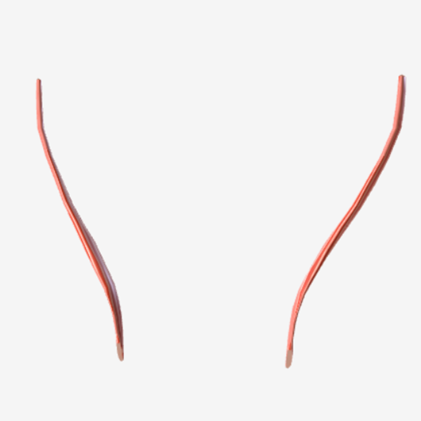

Salpingopharyngeus

origin is the lower margin of the auditory tube, coursing down to insert into the palatopharyngeus muscle; function is to elevate the lateral pharyngeal wall

Saplingopharyngeus

|  |  |

Salpingopharyngeus

C

Salpingopharyngeus

C